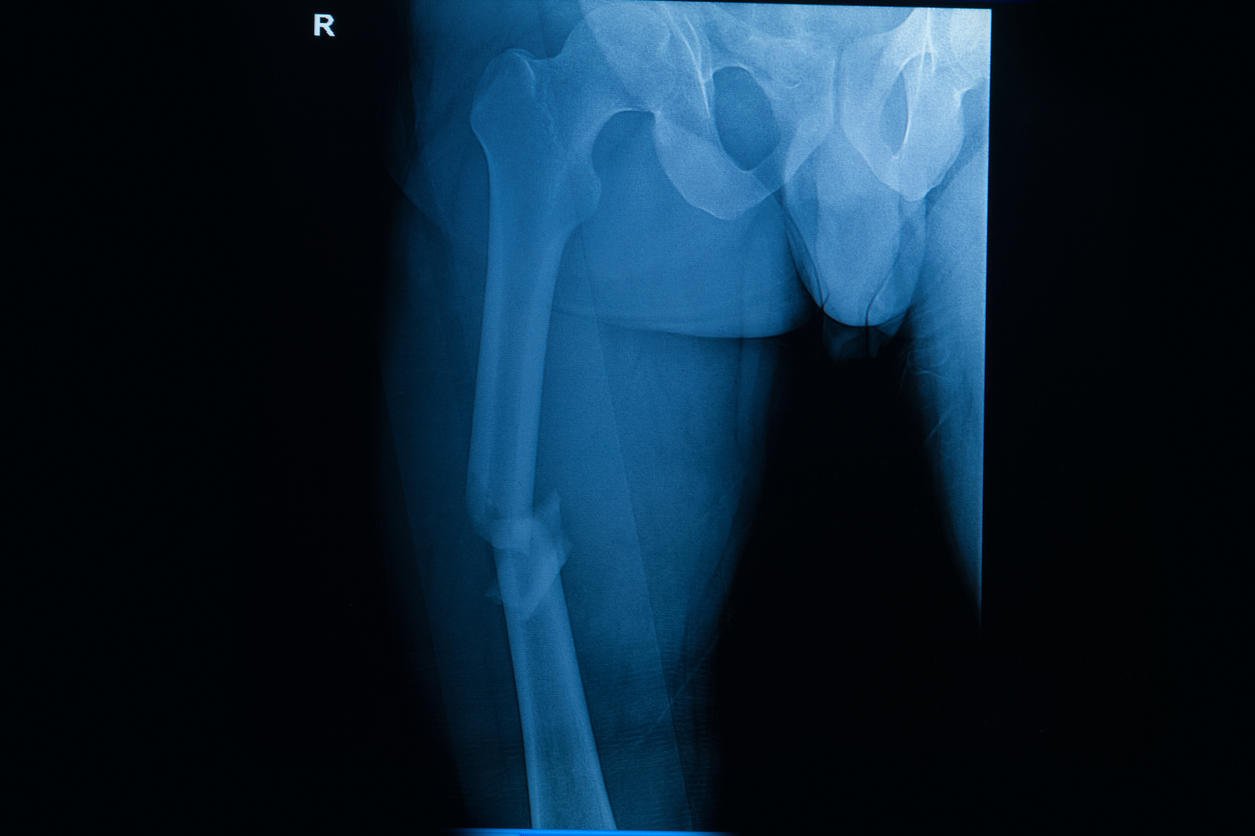

fracture radiographique du film fémur droit (cuisse droite)

Dans un premier temps on fait toujours une radio. « Il faut vraiment avoir l’œil, cela ressemble à un petit cheveu sur la radio », affirme le spécialiste qui précise : « La plupart du temps la radio sera normale.